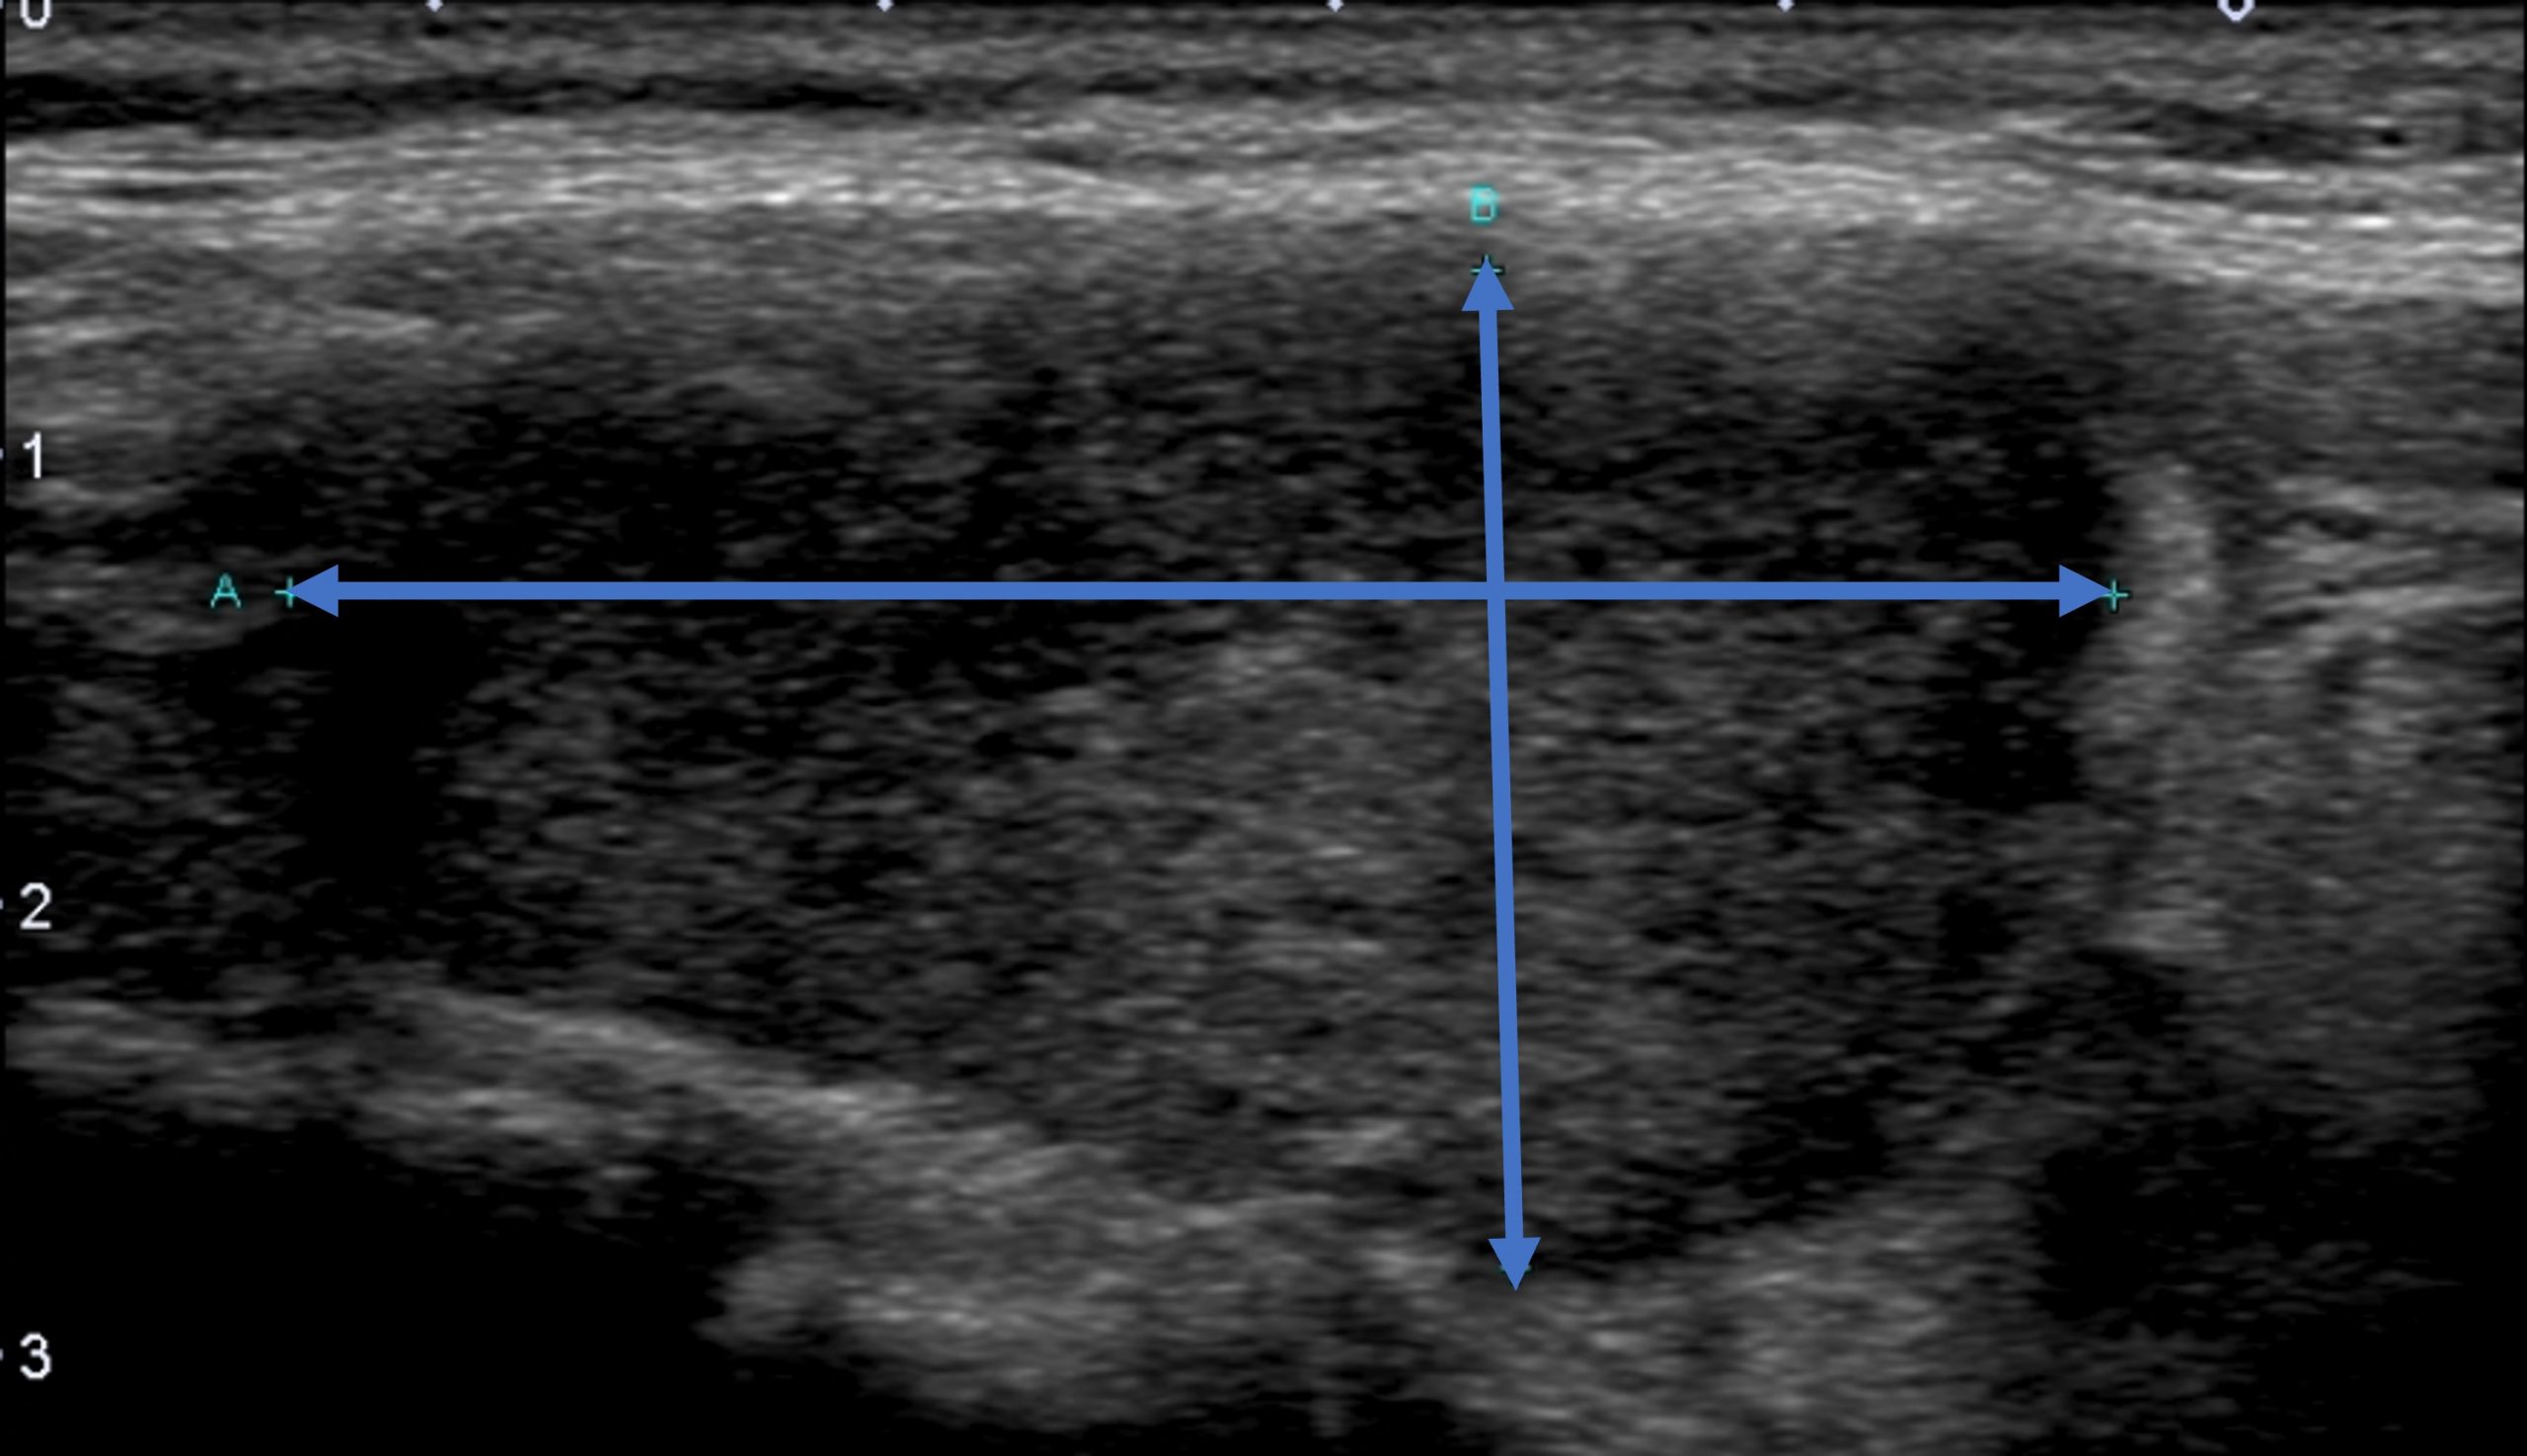

■実際の甲状腺エコーの画像■

甲状腺炎が炎症により著明に腫大・肥厚しています。

甲状腺エコーでは甲状腺の肥厚を認め、甲状腺の炎症を疑う状態でした。